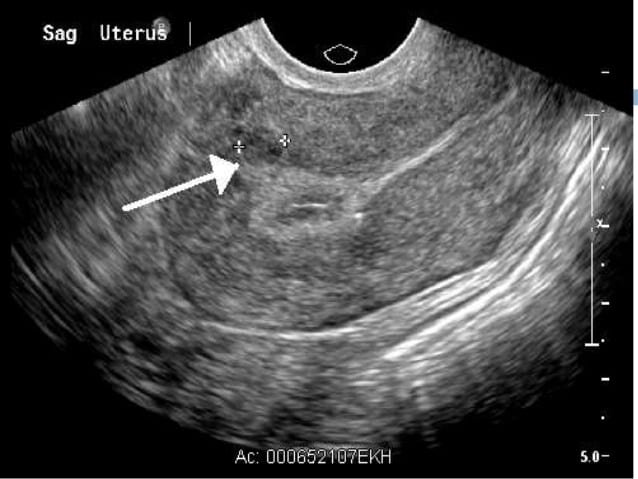

فیبرومها، تودههایی غیرسرطانی هستند که در بافت عضلانی رحم ایجاد میشوند و به گفته این پژوهشگران درصد قابلتوجهی از زنان تا ۵۰ سالگی خود ممکن است به آن مبتلا میشوند.

فیبرومهای رحمی میتوانند بیعلامت باشند و ممکن است با علائمی مانند پریودهای شدید و درازمدت، خونریزی میان پریودها و درد لگن بروز کنند.